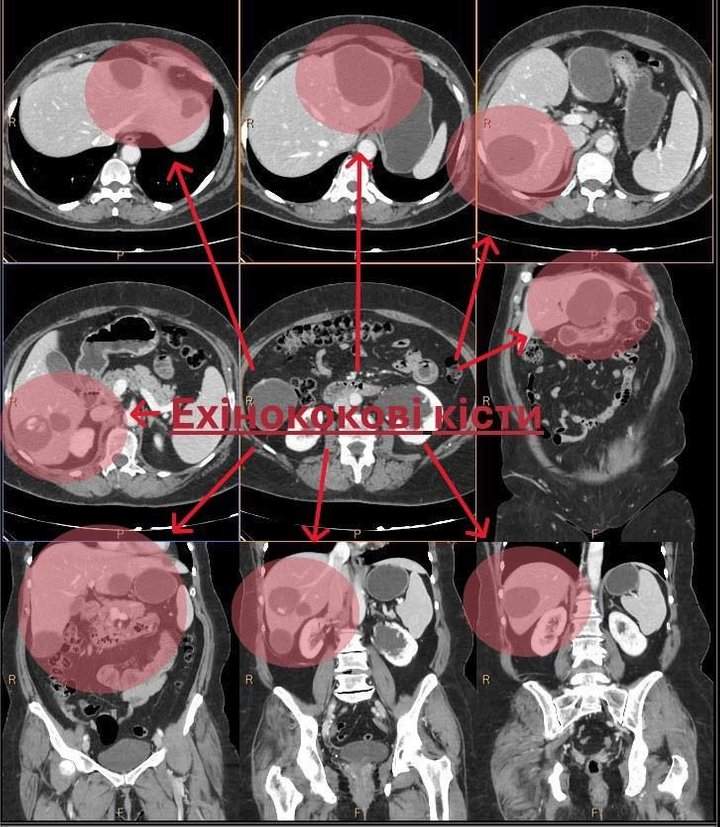

Як повідомили 15 серпня на сторінці медзакладу у фейсбуці, жінка звернулася до лікарів із низкою скарг, зокрема, на загальну слабкість, температуру, відчуття важкості у підребер’ї та животі. Після ретельного обстеження у печінці пацієнтки виявили ехінококові кісти – доброякісні паразитарні новоутворення, які з’являються в організмі людини внаслідок зараження личинками стрічкового червʼяка.

«Єдиним шляхом допомогти жінці було хірургічне втручання. Команда лікарів виконала операцію лапароскопічним методом. Завдяки спільній роботі вдалося повністю усунути патологічні вогнища та зберегти здорову тканину печінки. Пацієнтка почувається добре та перебуває на етапі відновлення», – повідомляють у лікарні.